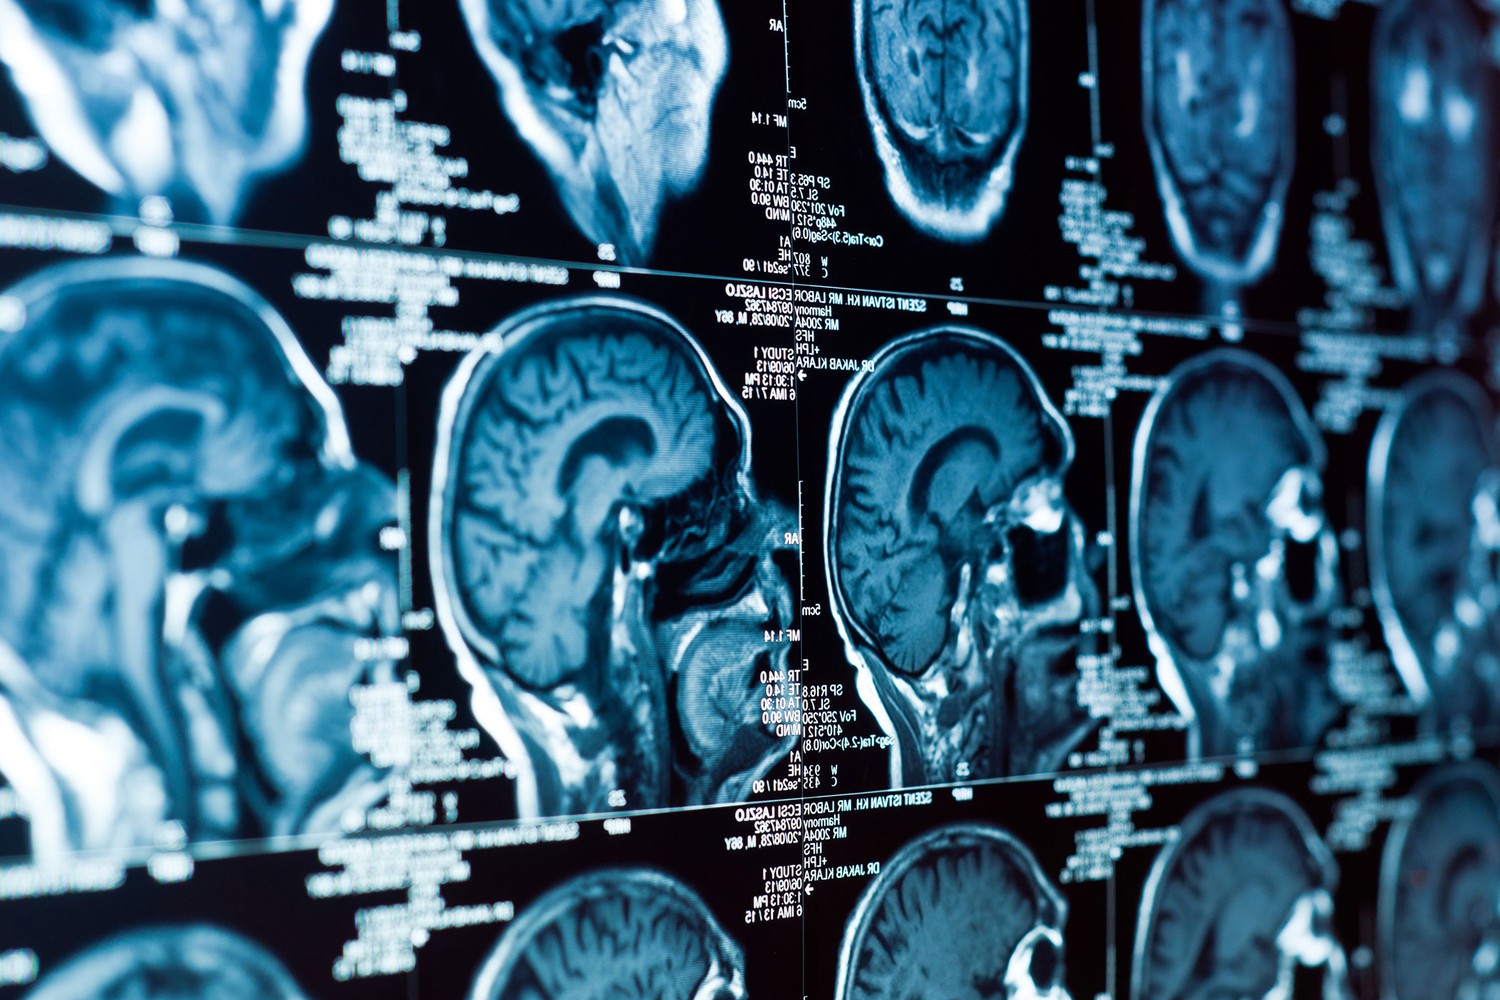

В ходе исследования специалисты изучили мозговую активность 148 добровольцев в возрасте от 18 до 60 лет, используя электроэнцефалографию (ЭЭГ). Они фиксировали колебания тета-волн (4–8 Гц) в среднелобной области мозга, которые активны при сосредоточенном мышлении и необходимости контролировать поведение.